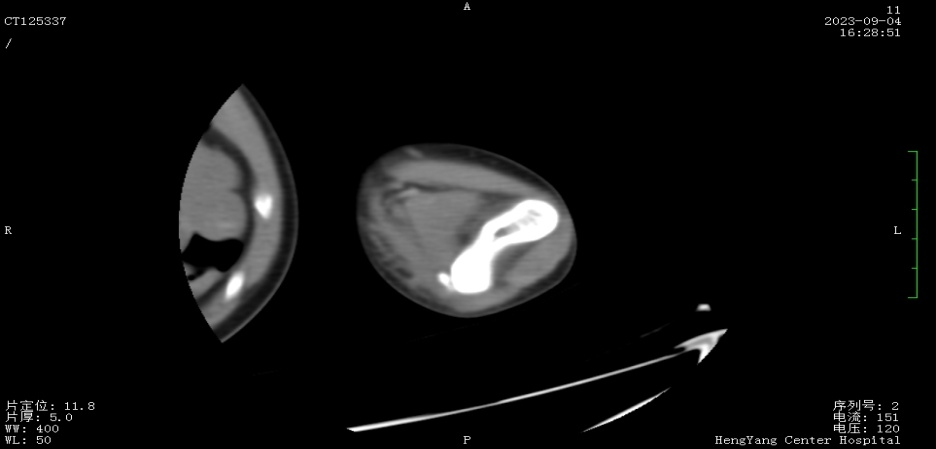

接診后,醫(yī)師發(fā)現(xiàn)小莫同學的左肘關節(jié)自然狀態(tài)下僅能伸展至約115°,并伴有習慣性屈肘。經(jīng)與骨科醫(yī)生溝通并閱片后,考慮骨化肌炎,針對這種情況,一般采取手法松解關節(jié)和關節(jié)功能鍛煉相結合的治療方案。但此方案常用于成人患者的關節(jié)粘連傳統(tǒng)松解術和關節(jié)松動訓練,對于兒童來說刺激強度太大,且因兒童骨骼及關節(jié)較成人脆弱,無法保證治療的連續(xù)性及安全性,若一味采取輕柔手法,不僅治療時間長、見效慢,還可能加重后續(xù)治療難度

面對這一難題,經(jīng)科室討論后,最終確定了以針刺運動療法為主的治療方案。正式治療時,康復醫(yī)師先用輕手法松解患處關節(jié)10分鐘后,使小莫同學手臂自然放松,后選取相應穴位后以寸針刺入,經(jīng)捻轉得氣后留針,并帶針運動5至10分鐘,出針后持續(xù)牽伸關節(jié)。

首次治療結束后,小莫同學的左肘關節(jié)即可伸展至145°。9月19日,小莫同學已結束第一階段共14次治療,他的左肘關節(jié)就可以自然伸展至170°,可滿足上肢基本功能需求。